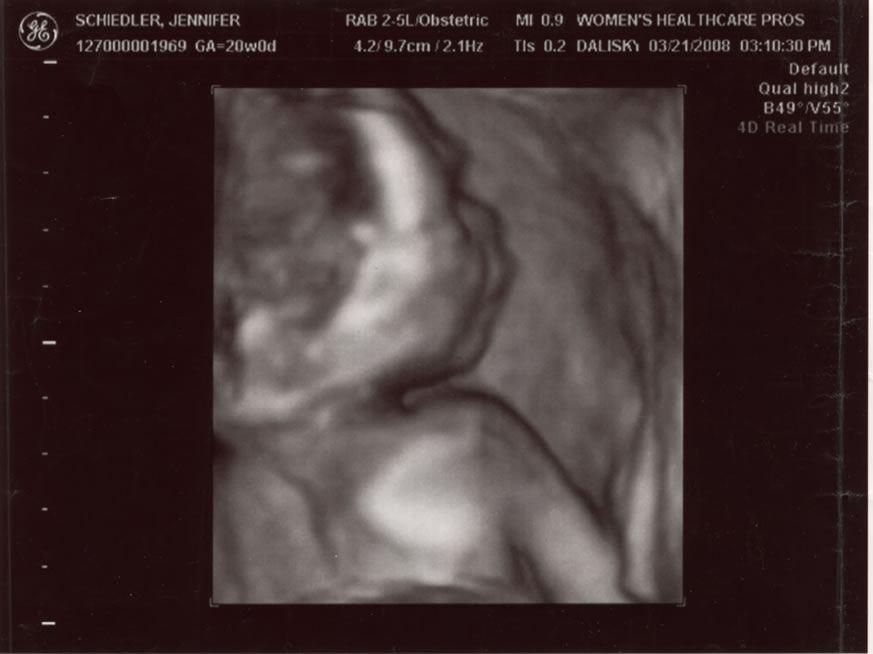

Profile  2 of 5